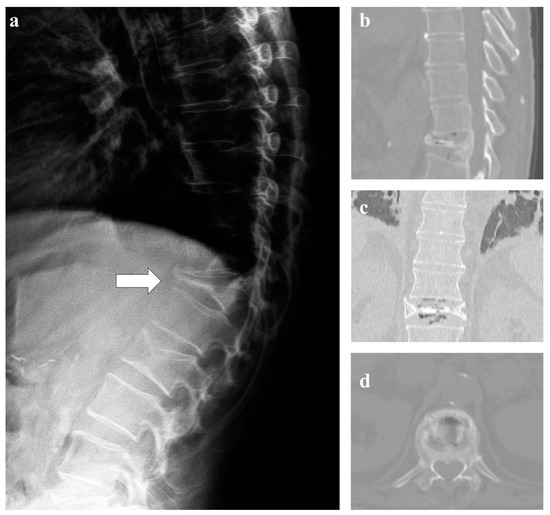

7. Osteoblastoma